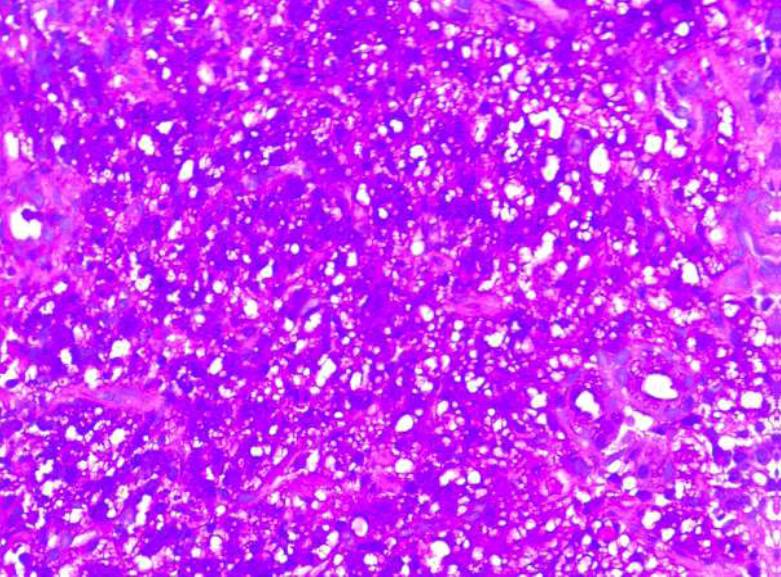

Thigh muscle biopsy done elsewhere was reviewed and it showed chronic granulation tissue without any evidence of granuloma or malignant cells. Blood cultures done did not show any growth. His bone marrow biopsy was unremarkable. He underwent a left thigh muscle biopsy which showed cores of fibrocollagenous tissue with stromal infiltrates of metastatic poorly differentiated mucin producing carcinoma, on immunohistochemistry (IHC) the tumor was positive for cytokeratin 7 and negative for Cytokeratin 20, GATA3, GCDFP 15, TTF1 and CD68) raising a suspicion of a primary neoplasm of upper GI tract. (Figure 3).

Figure 3a: Photomicrographs of trucut biopsy thigh mass showing nest of tumor cells with vacuolated cytoplasm (Hematoxylin & eosin x 400)